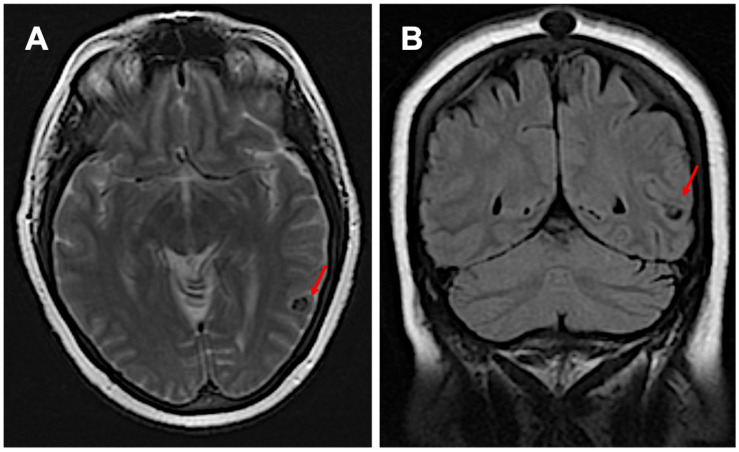

Neurocysticercosis (NCC), a parasitic infection caused by Taenia solium larvae, remains a leading cause of acquired epilepsy worldwide, particularly in regions with inadequate sanitation and healthcare access. We present a case of NCC reactivation in a 64-year-old female who developed anomic aphasia-a rare manifestation of NCC-decades after her initial diagnosis. The patient's clinical course was complicated by a potential trigger of semaglutide, which potentially attenuated the protective inflammatory response maintained by astrocytes and microglia, leading to the reactivation of dormant cysts. Brain imaging confirmed localized cystic changes, and treatment with antiparasitic agents and corticosteroids led to marked clinical improvement. This case highlights the complexity of NCC reactivation, highlighting the interplay of metabolic, immune, and parasitic factors. It emphasizes the need for vigilance in managing patients with dormant infections and investigating potential risks associated with novel therapeutic agents like GLP-1 receptor agonists. Further research is essential to unravel the mechanisms linking metabolic modulation to parasitic reactivation, offering insights into prevention and treatment strategies.

Abstract Image